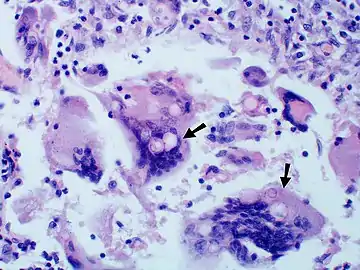

Large yeast-like fungi seen within giant cells at arrows.